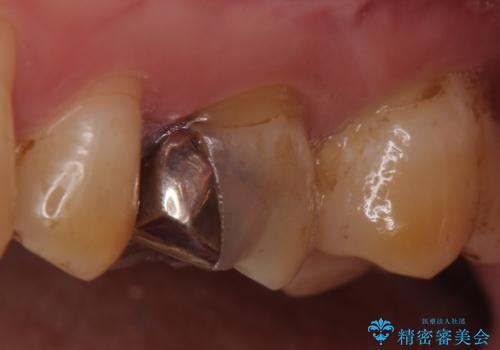

- ものを咬むと左上の奥歯が痛むので診て欲しいといらっしゃった方の症例です。

診査の結果、左上6が失活(歯の神経が死んでいる状態)しており根尖病変を認めたため、根管治療を行いました。

根尖病変の縮小及び症状の消失を確認後、オールセラミッククラウンによる補綴を行いました。